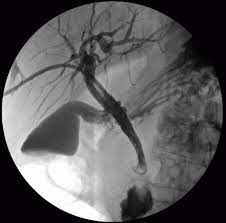

PERCUTANEOUS TRANSHEPATIC CHOLEDOCHOGRAPHY